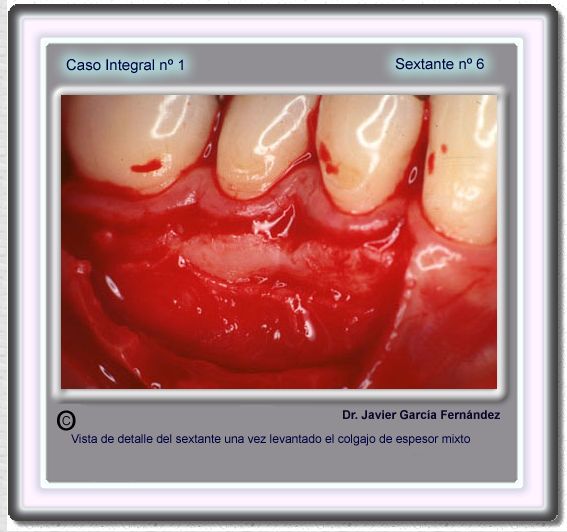

image 101